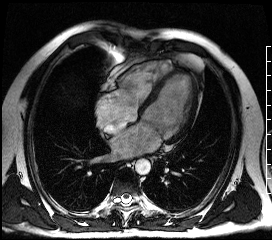

Что видит врач на МРТ сердца

Во время МРТ специалист не наблюдает орган в реальном времени, как при УЗИ. Аппарат собирает сигналы от атомов водорода в тканях, а врач следит за качеством данных и параметрами съёмки. Затем компьютер преобразует сигналы в послойные изображения — срезы в разных проекциях (короткая, длинная ось, четырёхкамерная проекция). Это статические снимки, на которых видна анатомия сердца.

Чтобы исследовать орган в действии, используют так называемый кинорежим (киноМРТ) — многократную съёмку одного и того же участка, синхронизированную с ЭКГ. После обработки врач получает видеопетли. На них можно видеть, как двигаются стенки, открываются клапаны и полости заполняются жидкостью. Именно эти кадры позволяют оценить фракцию выброса, регургитации и сократимость сердечной мышцы.

МРТ способна воссоздавать трёхмерную анатомию сердца, включая предсердия, желудочки, клапаны и перегородки. 3D-реконструкция позволяет рассмотреть сердце во всех плоскостях — что особенно важно при врождённых пороках и сложных аномалиях, а также при подготовке к операции.

Толщина и структура миокарда

Магнитно-резонансная томография сердца — единственный неинвазивный метод, который даёт информацию о структуре миокарда. Используя T1/T2-картирование и позднее контрастирование, врач может выявить:

отёк и воспаление — при миокардитах, остром инфаркте;

фиброз и рубцы — при постинфарктных и гипертрофических изменениях;

инфильтрацию (например, при амилоидозе или саркоидозе).

Такие данные невозможно получить с помощью ЭхоКГ или КТ сердца, потому что ультразвук передаёт строение и функцию органа, а компьютерная томография — состояние коронарных артерий и кровоснабжение миокарда.